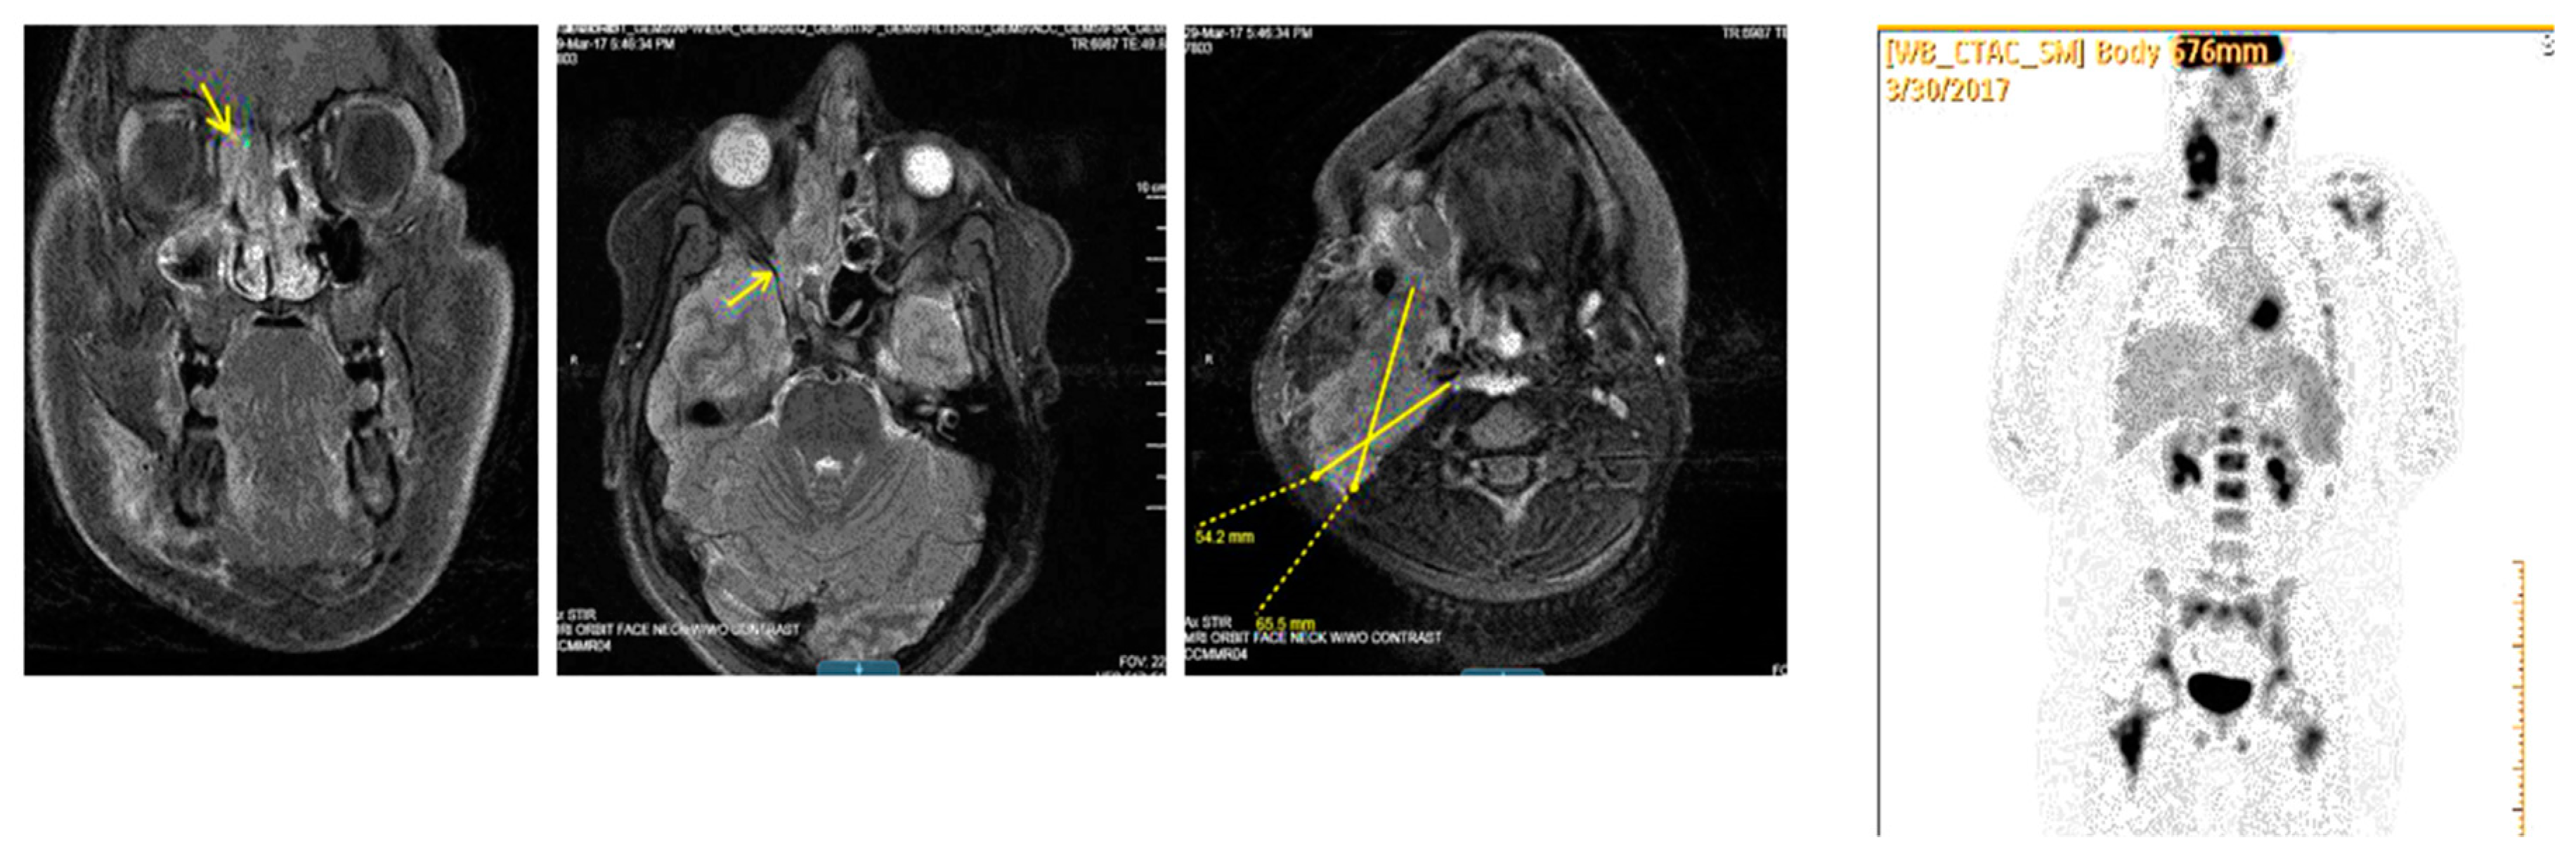

3. Presentation

4. Assessment

14. Assessment